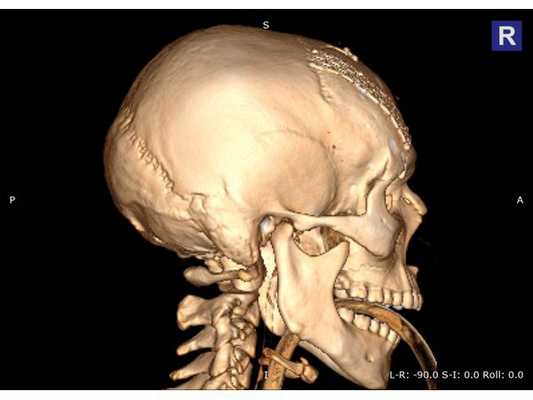

КТ головы (3D-реконструкция). Перелом лицевого черепа (скуловой дуги) и перелом в области лобно-скулового шва.